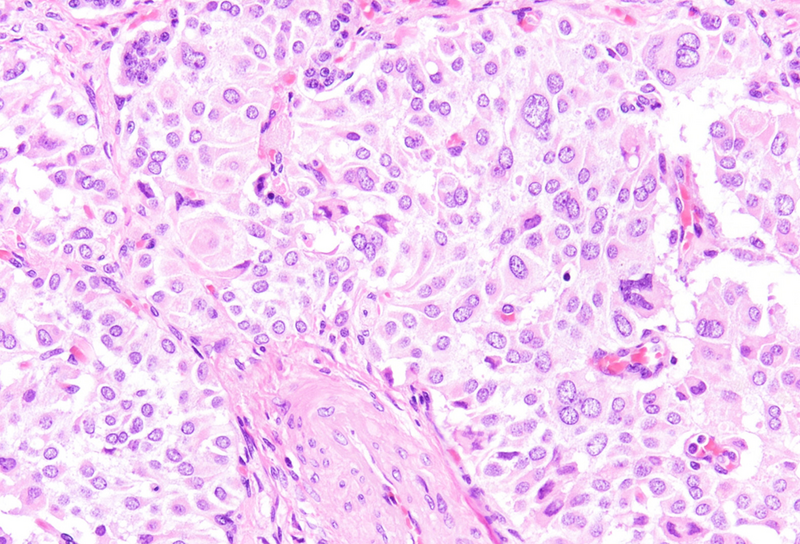

Histological examination revealed a well-circumscribed neoplasm with a fibrous capsule (Panel A), composed of uniform, poorly cohesive cells arranged in both solid (Panel B) and pseudopapillary structures (Panel C). The pseudopapillae resulted from degenerative changes leading to detachment of tumor cells from another and from central fibrovascular cores. Stromal hyalinization was also noted (Panel D). The neoplastic cells were monomorphic, with round to oval nuclei showing finely dispersed chromatin, inconspicuous nucleoli, and moderate amounts of eosinophilic to clear cytoplasm. Mitoses were not seen.